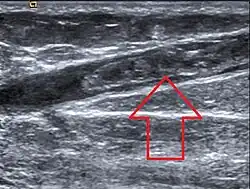

Die Diagnose einer Venenthrombose wird heute üblicherweise mittels Sonographie (Doppler- und Duplex-Sonographie) gestellt. Falls dieser nicht vorhanden ist oder nach der Ultraschalluntersuchung weiter Unklarheiten über das weitere Vorgehen bestehen, kommt die Phlebographie (Röntgenuntersuchung mit Kontrastmittel) zur Anwendung. Ist ein modernes Ultraschallgerät vorhanden und ist der Untersucher ausreichend erfahren, muss die aufwändigere und den Patienten belastendere Phlebographie nur noch selten zum Einsatz kommen.